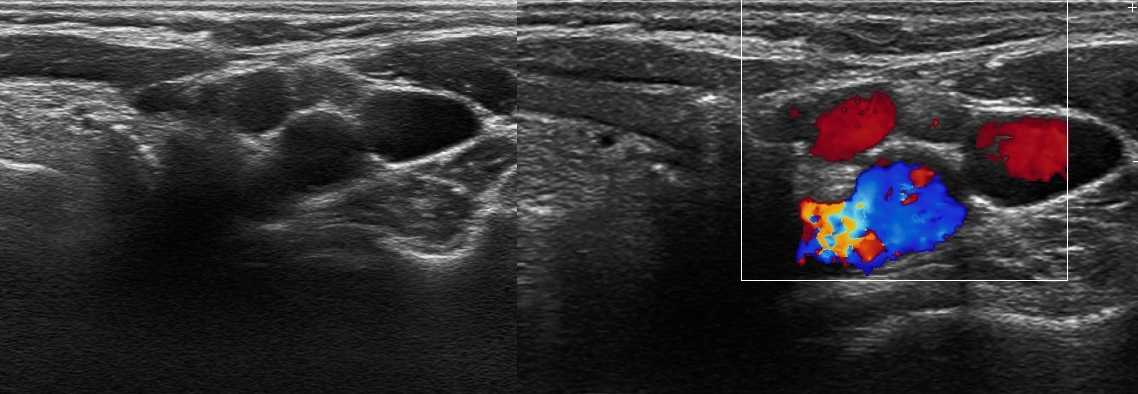

Рисунок. Женщина 65-ти лет с безболезненной «опухолью» в подмышке. На УЗИ определяется округлое образование с четким и ровным контуром, размер 20х10х15 мм; гипоэхогенный ободок по периферии и расширенная гиперэхогенная центральная часть; при ЦДК кровоток в гиперэхогенной зоне. Заключение: Подмышечный лимфоузел с жировой инфильтрацией мозгового вещества и переходной зоны.

Ангиоархитектоника нормального лимфоузла — различают воротную артерию, которая переходит в линейно расположенный сосуд в центральной части. Если сосудистое русло можно проследить до капсулы, а PSV на воротной вене выше 5 см/сек, говорят о высокой степени активности лимфоузла.